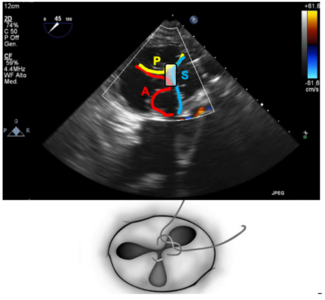

A 55-year-old male patient presented with a history of left ventricular assist device (LVAD) implantation due to ischemic cardiomyopathy. He was admitted to the cardiology department with progressive dyspnea. A HeartMate 3 (Abbott) had been...